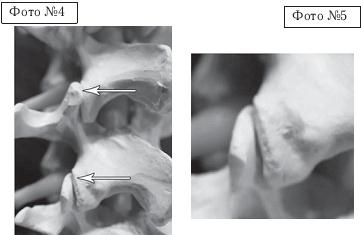

На фото № 6 макета позвоночника наблюдается смещение (подвывих) суставных поверхностей дугоотростчатых суставов. На фото № 7 наблюдается смещение (подвывих) суставных поверхностей дугоотростчатого сустава (увеличенный вариант). ![]() На фото № 8 макета позвоночника наблюдается перерастяжение дугоотростчатых суставов вследствие вытяжения. На фото № 9 наблюдается перерастяжение дугоотростчатого сустава (увеличенный вариант). ![]() Фото № 10 На фото № 10 макета позвоночника наблюдается нормальное взаимоотношение суставных поверхностей дугоотростчатых суставов, в норме высота межпозвонкового диска и межпозвонковых отверстий. ![]() Фото № 11 На фото № 11 макета позвоночника наблюдается смещение (подвывих) суставных поверхностей дугоотростчатых суставов. Подобное смещение, как правило, происходит вследствие развития дегенеративно-дистрофических процессов в межпозвонковом диске. При этом уменьшается высота диска, сужается просвет фораминального отверстия (межпозвонкового), что может способствовать ущемлению спинномозговых корешков (нервов) и сосудов. ![]() Фото № 12 На фото № 12 макета позвоночника наблюдается перерастяжение дугоотростчатого сустава вследствие вытяжения, расширение фораминального отверстия, а также растяжение задних отделов фиброзного кольца межпозвонкового диска и сближение вентральных (передних) отделов тел позвонков. Это приводит межпозвонковый диск в клиновидное состояние, что способствует выталкиванию содержимого межпозвонкового диска из передних его отделов в задние. |